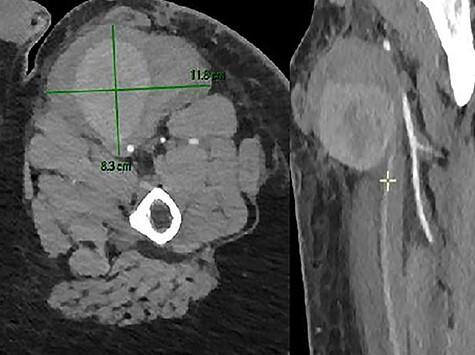

Spontaneous femoral artery pseudoaneurysm (PSA) is a rare disease and there are few reported cases. We report a case of a 17-year-old male with increasing left leg pain associated with swelling at the site of the pain. We observed a voluminous pulsatile mass. He had no history of trauma or surgery. Imaging confirmed a large PSA of the proximal portion of the left superficial femoral artery (SFA). The PSA was treated by resection of the aneurysm, reconstruction with inter-positional saphenous vein graft. Three months later; he came back to the emergency room for a pulsatile mass. The scan showed a PSA of his left SFA and a hematoma with active bleeding. It was treated surgically by resection of the aneurysm and reconstruction with graft.

自发性股动脉假性动脉瘤(PSA)是一种罕见疾病,报道的病例很少。我们报告一例17岁男性,左腿疼痛加重,疼痛部位伴有肿胀。我们观察到一个巨大的搏动性肿块。他没有外伤或手术史。影像学检查证实左股浅动脉(SFA)近端有一个大的PSA。通过切除动脉瘤、用大隐静脉间置移植进行重建来治疗该PSA。三个月后,他因搏动性肿块回到急诊室。扫描显示其左SFA有一个PSA和一个有活动性出血的血肿。通过切除动脉瘤并用移植物进行重建进行手术治疗。